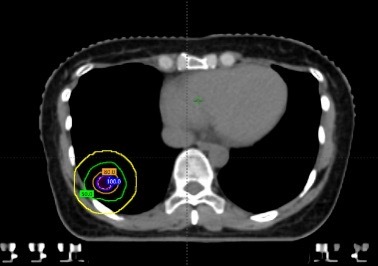

这三个病灶有几个共同特点:一是体积很小,直径均不到1厘米;二是位置分散,分别位于不同肺叶;三是其中一个紧贴肋骨,几乎没有“安全距离”。

在治疗前,团队通过四维CT对三个病灶进行精准定位,尤其是紧贴肋骨的那个病灶,连与肋骨之间极其细微的间隙都被清晰标注出来。

随后进入最核心的剂量设计环节。医生与李忠伟、雷大明物理师反复推演射线路径和强度分布,把高剂量区域严格控制在肿瘤范围内,同时让剂量在极短距离内迅速下降。可以理解为,在体内完成了一次“毫米级雕刻”:肿瘤被精准覆盖,而近在咫尺的肋骨却被保护在安全范围内。